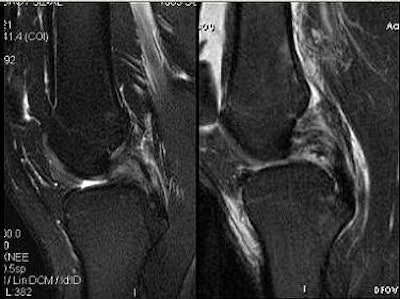

![]() |

Above, PCL tears that are likely to heal. Below, PCL tears that are not likely to heal.